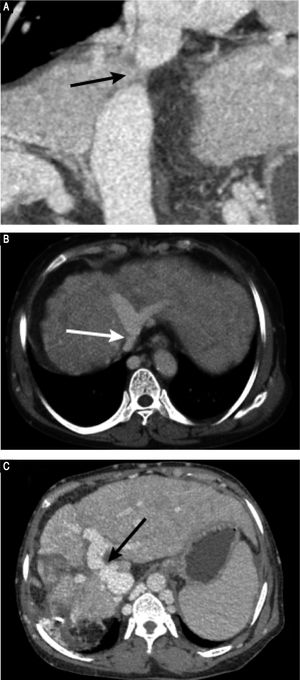

Based on these findings, we performed percutaneous balloon angioplasty (PTBA) for the obstructed IVC. For the Abernethy malformation, we elected conservative treatment because the patient was asymptomatic and the diameter of the shunt was small. For the PTBA procedure, we first performed inferior vena cavagraphy through the right femoral vein to identify the anatomy and location of the occluded section of the IVC (Figure 3A). Next, a selfmade, blunt, steel wire needle was introduced transfemorally into the distal portion of the obstruction to rupture the obstructive membrane of the IVC. A super stiff exchange wire was then inserted and positioned in the superior vena cava through the obstructed IVC. PTBA of the IVC membranous obstruction was performed with a 25 mm diameter balloon catheter (Cook Medical, Bloomington, IN, US) (Figure 3B). After the PTBA, the IVC pressure had decreased from 19 to 10 cm H2O, and inferior vena cavagraphy revealed adequate IVC blood flow and no stenosis (Figure 3C).

Digital subtraction angiography images. A. Inferior vena cavogram via both the jugular approach and the femoral approach reveal complete obstruction of the intrahepatic IVC, which confirmed the results of Doppler ultrasound and CT-angiography. B. Dilation of the obstructed IVC with a 25 mm diameter balloon after successful rupture of the membrane, C. Inferior vena cavogram immediately after balloon angioplasty reveals patency of the IVC without residua stenosis.